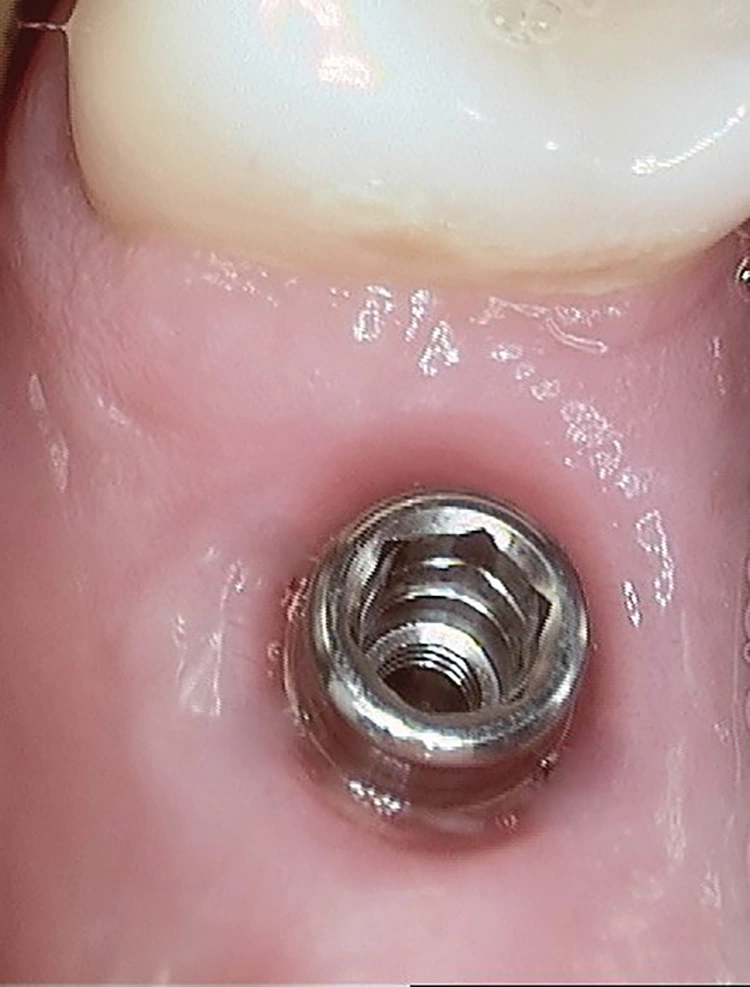

Insertionen nach dem MIMI-Protokoll funktionieren am besten mit zweiteiligen Champions (R)Evolution-Implantaten, die für dieses Insertionsprotokoll optimiert wurden. Diese Implantate werden beispielsweise bereits ab Werk mit der definitiven Halteschraube und dem ersten Gingivaformer, dem Shuttle, ausgeliefert.

Eine zeitsparende, supragingivale Abformung (ohne mehrfach verschiedene Hilfsteile auf- und abzuschrauben, die das Implantat-Innengewinde malträtieren können) sowie die „Nicht-Wiedereröffnung“ in der prothetischen Phase sind ebenfalls im MIMI-Protokoll definiert. Dies gilt auch für Multi-Unit Abutments.